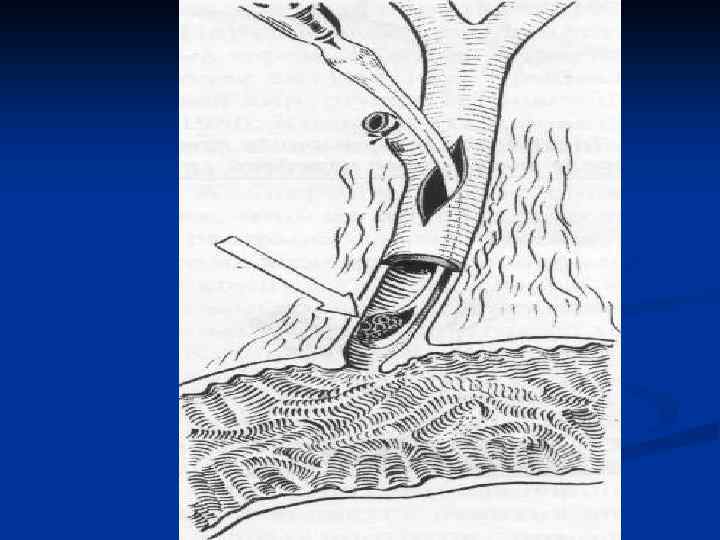

Лечение холангиолитиаза Холангиолитиаз устраняется с помощью эндоскопических методов после выполнения РХПГ. Выполняется эндоскопическая папиллосфинктеротомия в сочетании с удалением камней из холедоха петлей Дормиа, катетером Фогарти n Лапаротомия с холедохотомией – альтернативный метод лечения. n

Лечение холангиолитиаза Холангиолитиаз устраняется с помощью эндоскопических методов после выполнения РХПГ. Выполняется эндоскопическая папиллосфинктеротомия в сочетании с удалением камней из холедоха петлей Дормиа, катетером Фогарти n Лапаротомия с холедохотомией – альтернативный метод лечения. n